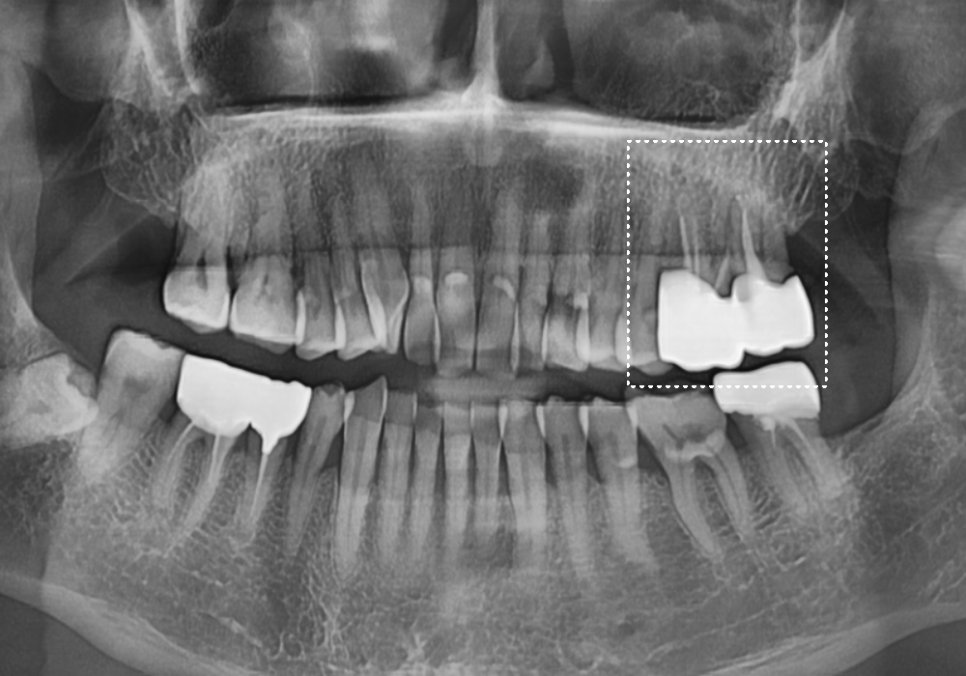

왼쪽 위 어금니 두 개(#26, #27)가 동시에

시큰거려서 내원하셨는데요~

입안을 살펴보니 전체적으로

치아가 많이 닳아 있었고,

정밀 CT를 통해 분석해 보니,

치아에 금이 가 있는게 보입니다.

다행히 환자분은 만 65세가 넘으셔서

건강보험 임플란트 혜택을 받으실 수 있었는데요~

부담스러운 비용을 크게 낮추어

임플란트 수술을 진행하셨고,

260429

3개월 뒤 임플란트 기둥과 뼈가

단단히 굳은 것을 확인하여

최종 지르코니아 보철물로

아주 튼튼하게 마무리해 드렸습니다. ^^